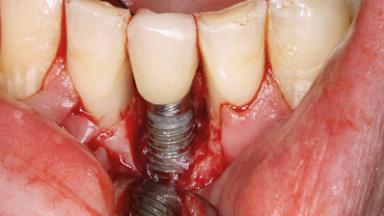

Peri-implantitis Treated with Access-Flap Surgery

A 27-year-old male was referred to the periodontist for assessment and management of implant site 41. The implant had been placed nine years previously and restored with a screw-retained single crown. The patient was a cigarette smoker in good general health. He reported he had reduced his smoking habit from 25 cigarettes per day to 15 cigarettes per day in the previous six months. On examination, there was calculus and plaque present at the lower anterior teeth and at implant site 41. Localized attachment loss was observed at teeth 32 and 42, with 2–3 mm of gingival recession. At implant site 41, there were 8–9 mm probing depths with suppuration and bleeding on probing.